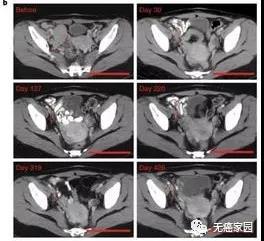

这项早期的临床试验招募26例难治性B细胞淋巴瘤患者,其中25例得到治疗。结果显示,在抗击癌症方面,改良CAR-T疗法表现出色,在低剂量和中等剂量组中,均有一半患者获得临床缓解。而接受最高剂量的11例患者中,6例(54.5%)完全缓解,2例(18%)部分缓解,提示这款经过改良的CAR-T疗法,疗效没有打折扣。

这些数据表明,CD19-BBz(86)CAR-T细胞具有强大且持久的抗肿瘤作用。

在研究者更为关注的安全性上,这款新型CAR-T疗法也是表现不俗。在25例患者中,无一例患者出现1级以上的细胞因子释放综合征。更可喜的是,无任何患者出现CAR-T疗法另一常见副作用神经毒性。无一例患者需接受药物治疗来缓解副作用。对比现有获批的CAR-T疗法(超过一半受细胞因子释放综合征困扰,约四分之一有神经毒性),这种新CAR-T疗法初步研究成果令人振奋。